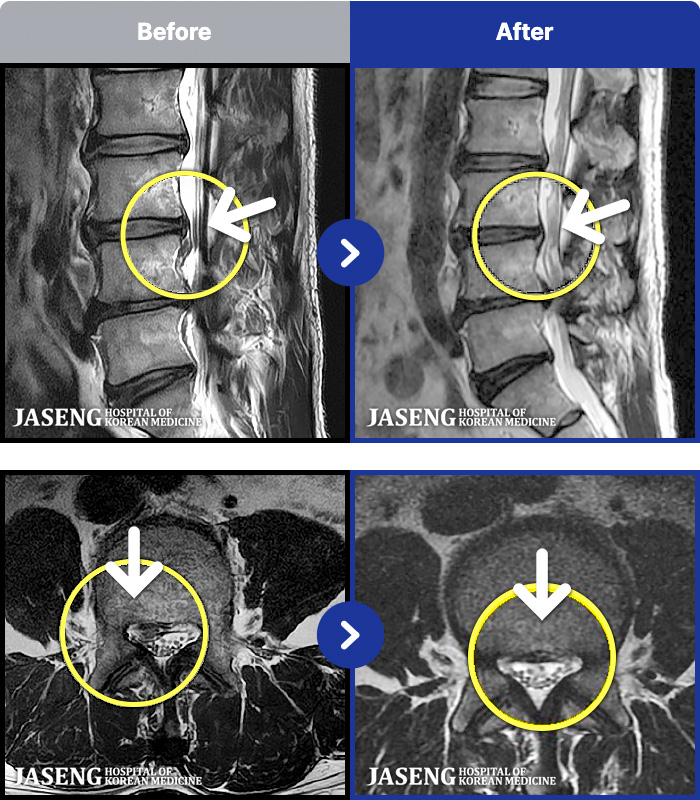

MRI ġ

54 MRI ũ ʸ Ȯϼ.

54

[Կñ:22.04.11~22.07.28]

[_㸮ũ] Ͽ ü Ÿ Ͽϴ.

No.54

ȸ 163

2026.01.09